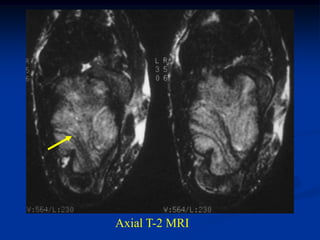

Axial T-2 MRI

Axial T-2 MRI showing large hemorrhagic pseudotumor